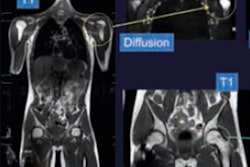

CAD reference data and detections. Left: reference lesions (yellow: sclerotic, cyan: lytic, purple: mixed). Middle: detections before classification. Right: detections after classification (green: true positive, blue: false positive).The project used fused PET/CT images because they have been shown to increase tumor detection over the use of CT alone in clinical studies, Summers said. The researchers combined the modalities with the use of synthetic fused images to utilize the higher dimensional operation capability of computers.

Two image sets were produced for each study by integrating PET with CT data, with one set for lytic and the other for sclerotic lesions, and PET used for density amplification. Creating the synthetic images involved a simple linear transform where the original images were combined using a weighting factor that was determined empirically from a few training cases, Summers explained.

"In essence, we increased the CT attenuation of the images for sclerotic lesions and decreased the CT attenuation of the lytic lesions based on the intensity of the PET images," he said.